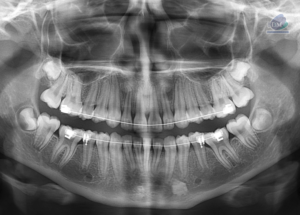

Paciente masculino de 20 años de edad, es referido al Instituto de Diagnóstico Maxilofacial – IDM por dolor en zona mandibular.En la radiografía panorámica (Figura